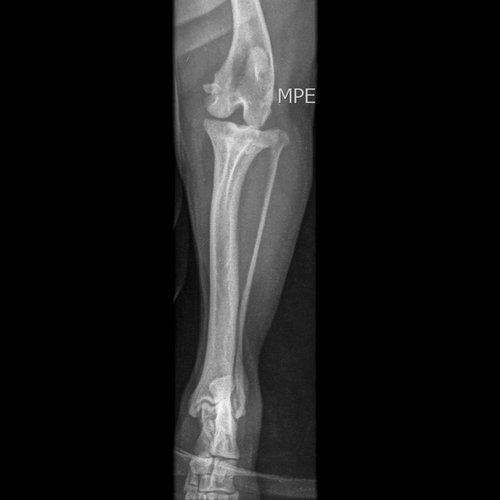

Meu nome é Gedilson, estou fazendo esta vaquinha para fazer a cirurgia do Thor (Lhasa Apso) que pulou da cadeira e teve uma fratura na perna esquerda traseira (exames abaixo). no hospital público aqui de Santo André não foi possível fazer pois não tinham as ferramentas necessárias que segundo eles custam 18 mil reais.